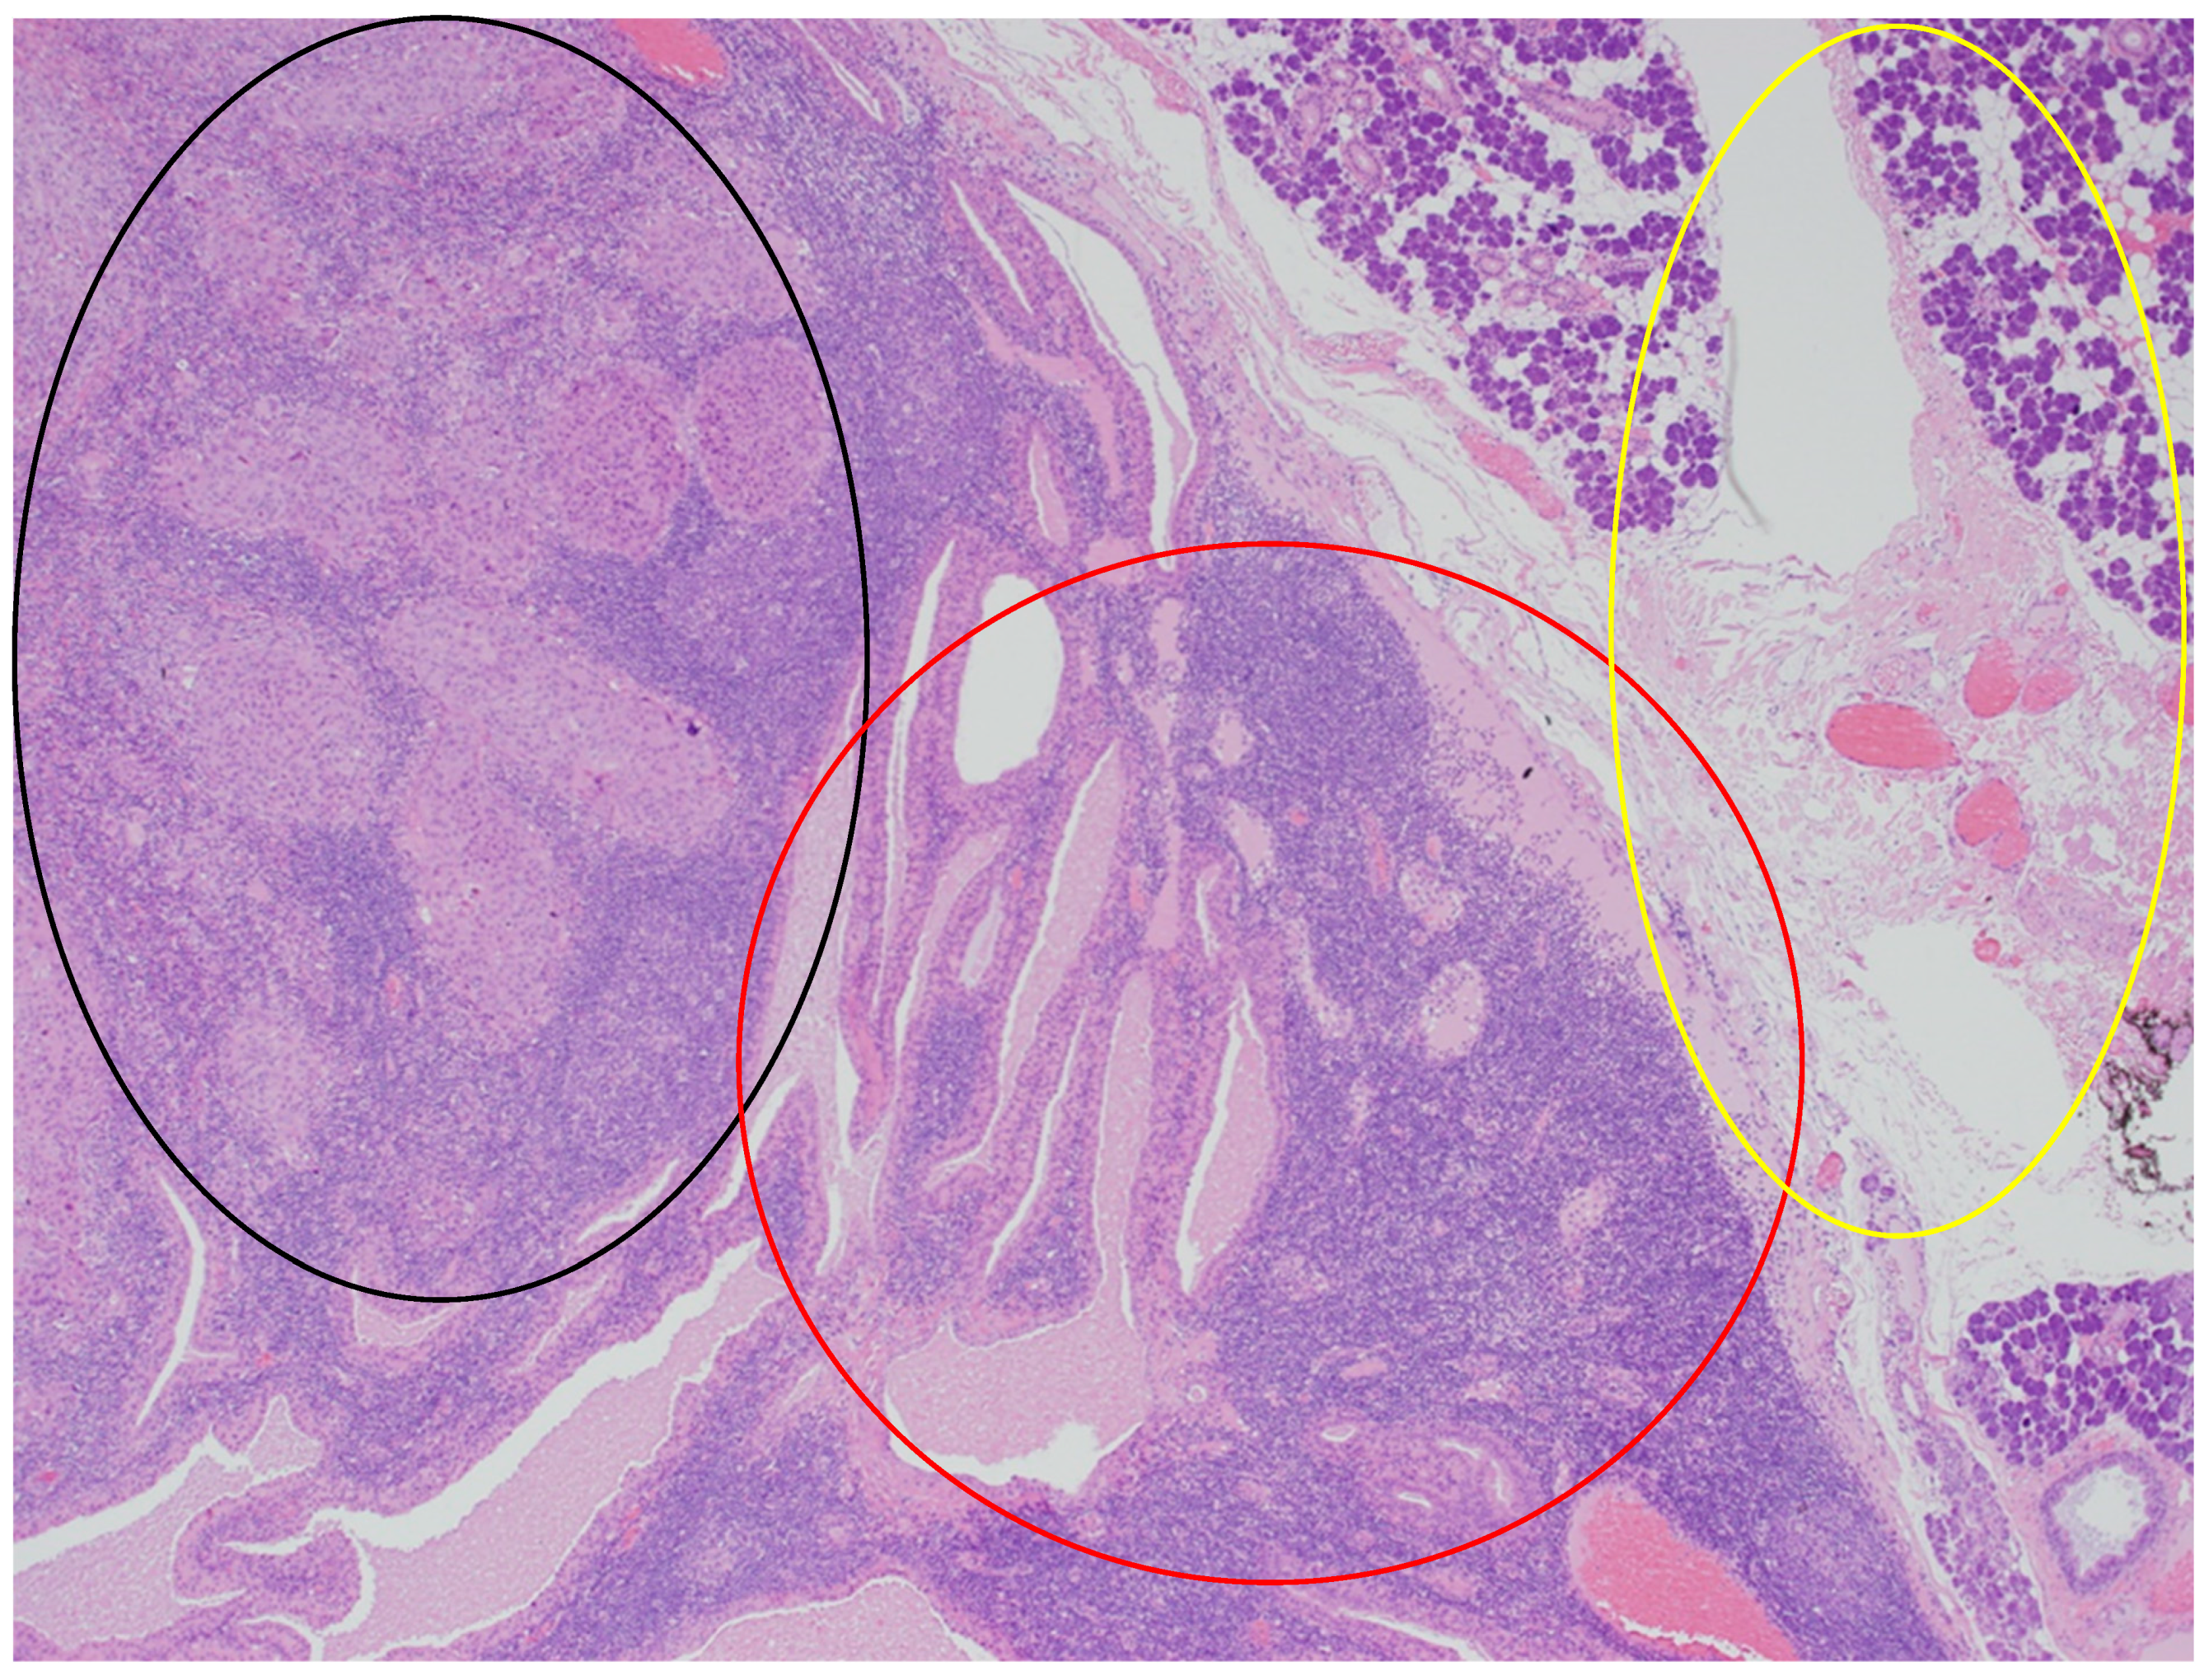

In the histopathological examination of the remaining components of the surgical specimen, a parotid Warthin tumor was found; in the majority, it was occupied and destroyed by the metastatic squamous carcinoma (with the largest metastasis dimension of about 24 mm) (Figure 3, Figure 4 and Figure 5) and radically removed. A second small parotid Warthin tumor, not involved in the cancer metastasis, was removed nearby. Additionally, a cancer metastasis 10.7 mm in diameter in the intraparotid lymph node and a small lymph node with cancer metastasis 1.4 mm in diameter were found, without extranodal extension (ENE-), and were also completely removed. The examination of 12 lymph nodes in the neck specimen did not reveal metastases; thus, the final pathological stage established, according to the 2017 AJCC classification, was pT3N2b (ENE-) with LVI2, PNI0, and R0.

Figure 4.

The parotid Warthin tumor, with the benign epithelial cystic component in the central and right parts of the photo (red circle), with the rim of parotid gland tissue not involved in any neoplasm on the right (yellow circle), and the squamous cell carcinoma metastasis in the superior left part (black circle). HE staining. Magn. ×88.